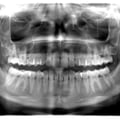

Пацієнт Б (14 років) - множинна ретенція прорізування постійних зубів. Наявність закладки 9-тих зубів